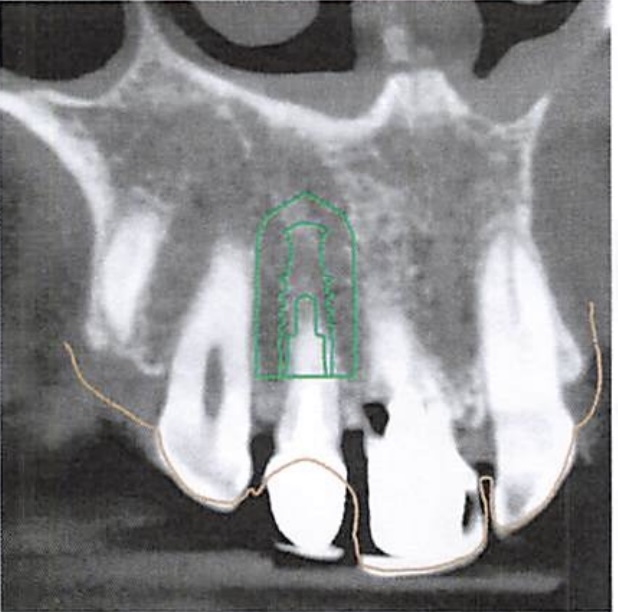

3D Imaging

We map bone density, nerve pathways, and surrounding structures. This is the foundation for everything.

Digital planning

We determine exactly where your tooth needs to sit — for proper function and natural aesthetics.

The planned position is translated into a precision guide that directs placement during surgery.

No estimation — the thinking is done beforehand.